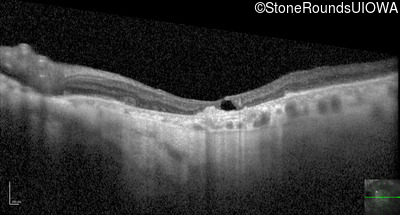

Optical Coherence Tomography - Right - 20/80

Exemplar / OCT Stack